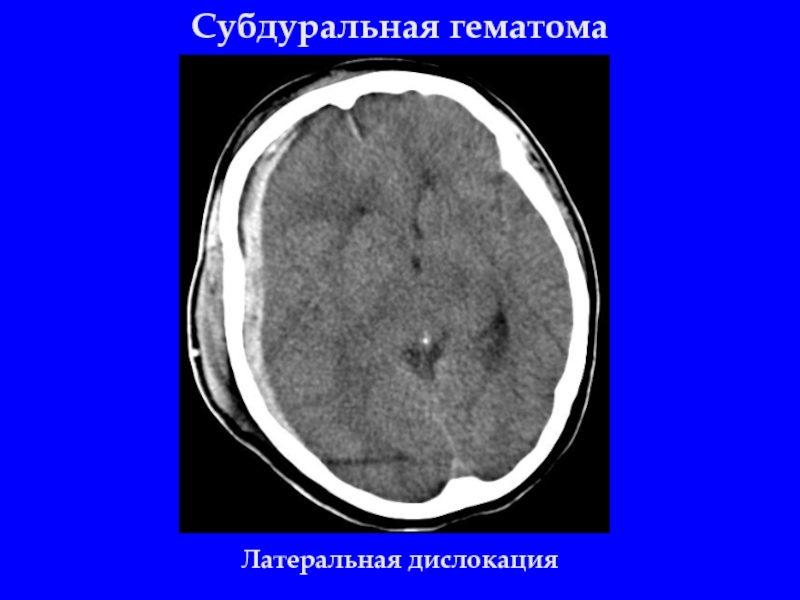

Слайд 17Субдуральная гематома

Латеральная дислокация